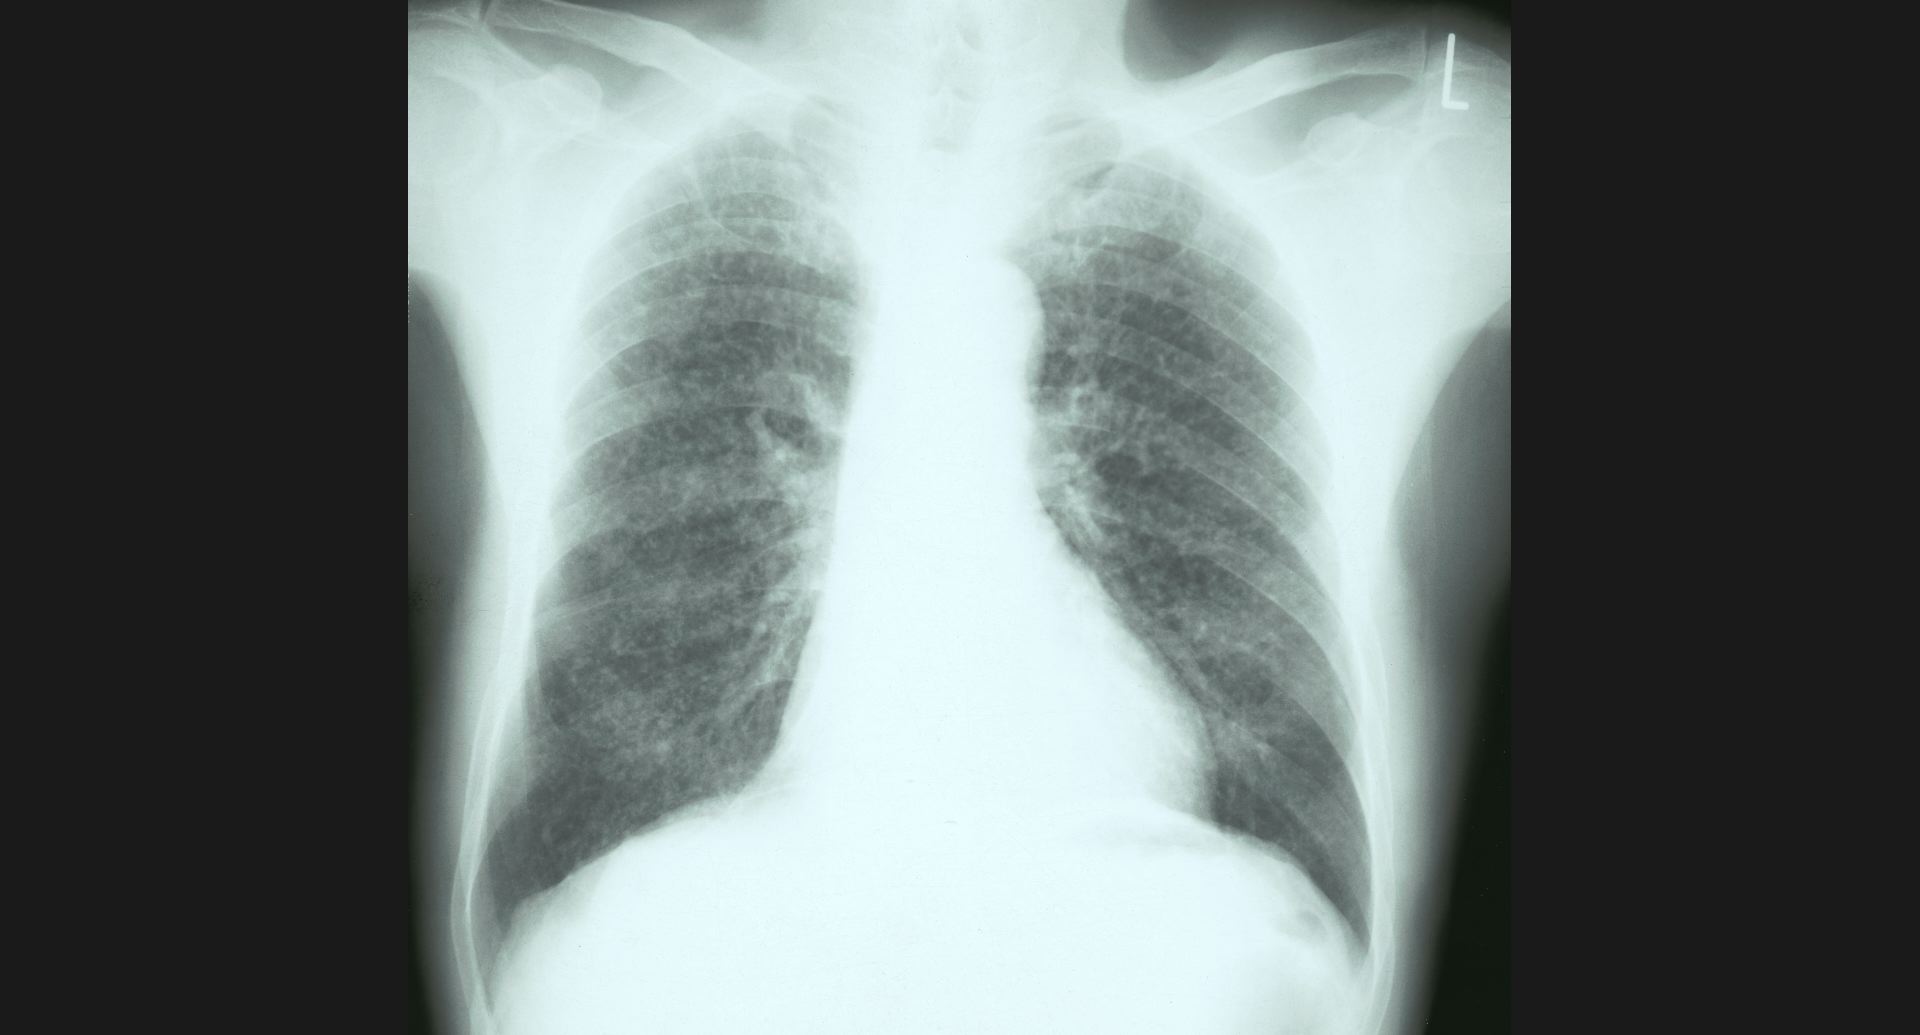

fig.1(117KB) :Alveolar microlithiasis

細かい肺病変、air bronchogram。